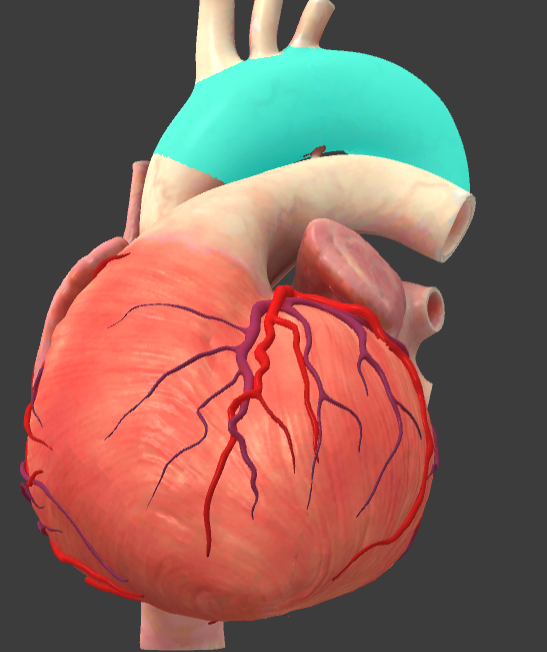

What is the name of the main vessels that supply the heart tissue with blood?

Coronary arteries

Right coronary a.